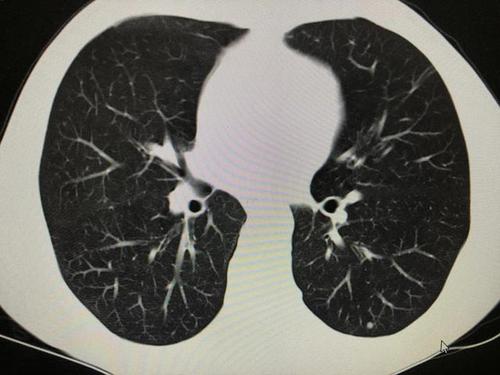

肺结节读片(14):不需要随访的的良性肺结节

肺部什么样地小结节是早期肺癌,对比良性小结节图

恶性良性肺结节图片

良性肺结节图片

肺结节良性与恶性鉴别

恶性肺结节图片

良性肺结节ct图片